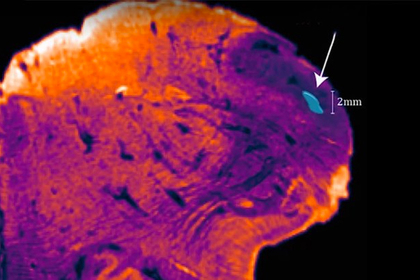

В человеческом мозге обнаружена неизвестная прежде структура, названная учеными научно-исследовательского института неврологии Австралии (Neuroscience Research Australia) ядром веревчатого тела (endorestiform nucleus). Пока никто не знает функций этого образования. Об этом сообщает издание Science Alert.

Известно, что ядро расположено в нижней ножке мозга (веревчатого тела), это сгусток нервных волокон. По нему от спинного мозга в мозжечок идут импульсы. Тело при этом регулирует осанку, равновесие и движение тела.

Endorestiform nucleus — группа обособленных нейронов, играющая ключевую роль в функциях ножки мозга.

Анатомическая структура была обнаружена при применении новой методики окрашивания некоторых тканей мозга. Красители связываются с нейромедиаторами и специфическими ферментами, в данном случае с ацетилхолинэстеразой.